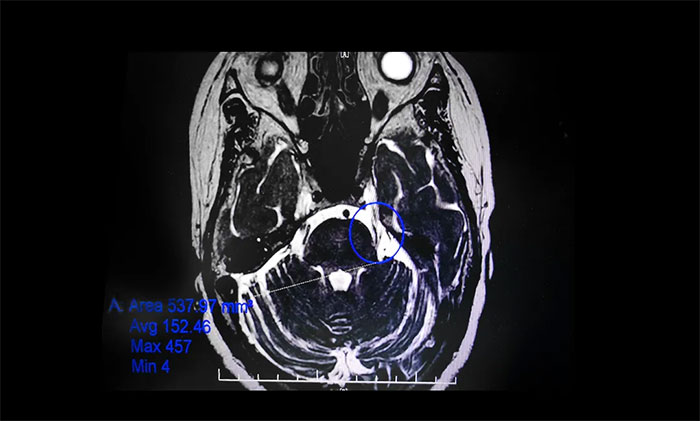

▲ 影像显示,患者左侧三叉神经与周围小血管关系密切

在办理入院手续后,杨忠旭教授详细了解了陈阿姨的病史资料,并为其申请了三叉神经MRTA平扫+增强等相关检查。结合影像资料,杨忠旭教授指出患者左侧三叉神经与周围小血管关系密切,手术指征明显,未见明显手术禁忌症。